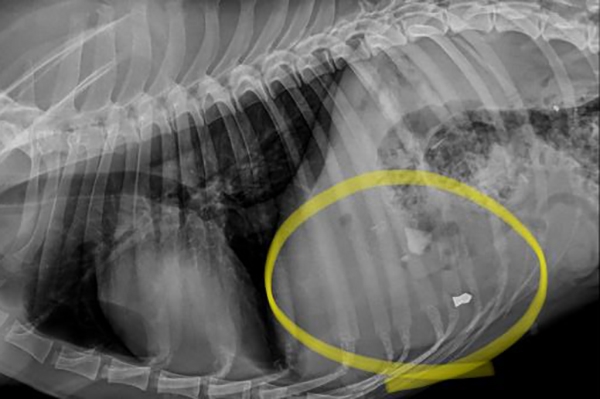

Como não bastassem os machucados nas orelhas e olhos de Cacau, ele também tem um projétil no tórax. Isso quer dizer que alguém atirou contra o animal. De acordo com a equipe que está cuidando do cachorro, não é possível retirar a bala, mas ele vai precisar passar uma cirurgia oftálmica e tratar seus problemas de saúde.